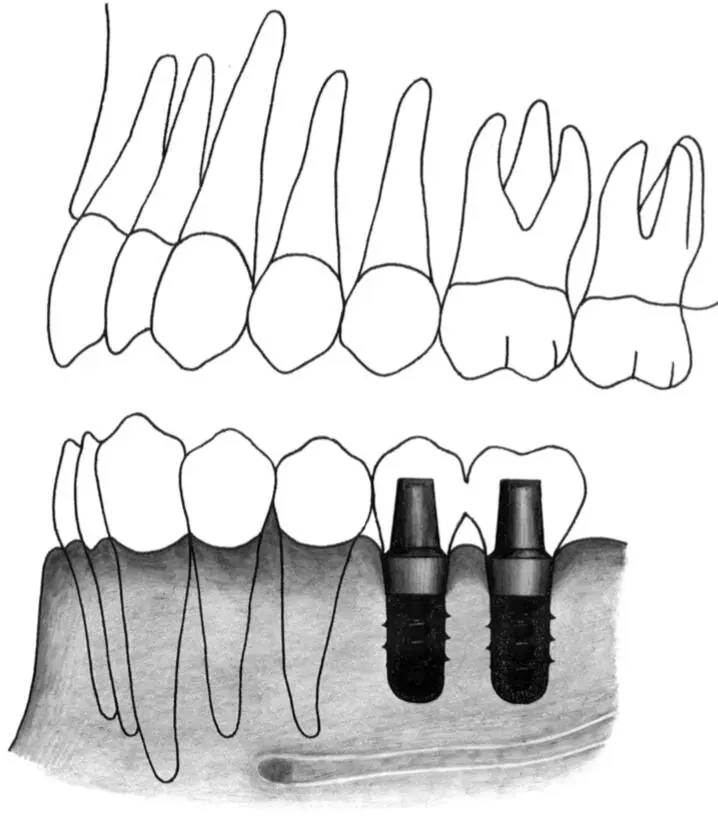

Figs 1-11i and 1-11j Occlusal (i) and lateral (j) views of implants positioned in the first premolar and first molar sites. In this extended posterior distal extension situation, a regular neck implant and a wide neck implant are indicated as abutments for a three-unit fixed partial denture. The regular neck implant is positioned 4 to 5 mm from the tooth. The wide neck implant is inserted about 16 mm from the anterior implant.